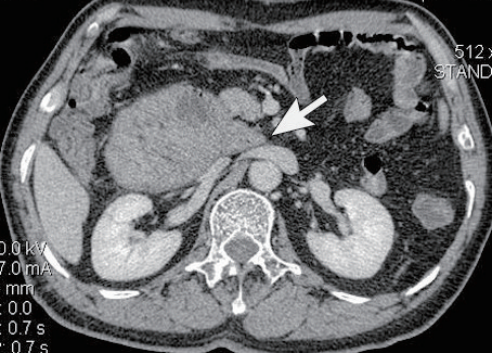

患者男性,62岁,上腹痛伴呕吐1天,加重3小时。

右侧十二指肠旁疝

图3 增强CT扫描肾下极水平,肠系膜上动、静脉(箭号)右侧可见环形肠绊(箭头);

在十二指肠旁疝中,以小肠内疝最为常见,约占所有内疝的50%,但右侧十二指肠旁疝相对少见,与小肠系膜-腹膜融合失败,于小肠系膜根的中上部形成小肠系膜根壁窝-Waldeyer窝相关,十二指肠空肠曲及空肠近段疝入囊内,肠系膜上动脉与静脉位于疝口。患者临床表现为小肠高位梗阻的症状。利用CT的薄层大范围扫描可清楚显示疝的解剖,并做出正确诊断,提示临床应对系膜缺损修补。